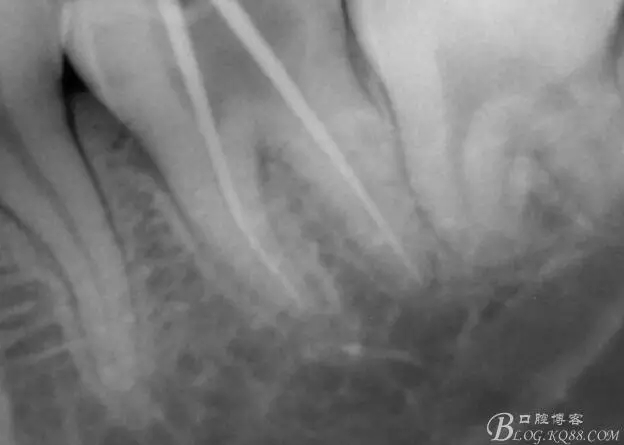

口腔檢查:37頰頜面齲洞,叩(+),探(+),冷熱測(cè)試與對(duì)照牙對(duì)比為敏感。17 27 47 均有不同程度齲壞,無(wú)明顯陽(yáng)性體征。18 28 38 48 呈不同程度傾斜,38 48牙冠部分萌出。全口牙齒排列不整齊,口腔衛(wèi)生較差,牙石(++),部分牙齦發(fā)紅。X線檢查示37牙冠低密度影像累及牙髓,牙周間隙略增寬。

一周后復(fù)診,37叩(—)。去除暫封物,沖洗,試主尖拍片。

X線示牙膠尖到達(dá)工作長(zhǎng)度,故行AH-PLUSH糊劑配合卡瓦熱牙膠機(jī)運(yùn)用連續(xù)波充法根充,暫封拍根尖片。